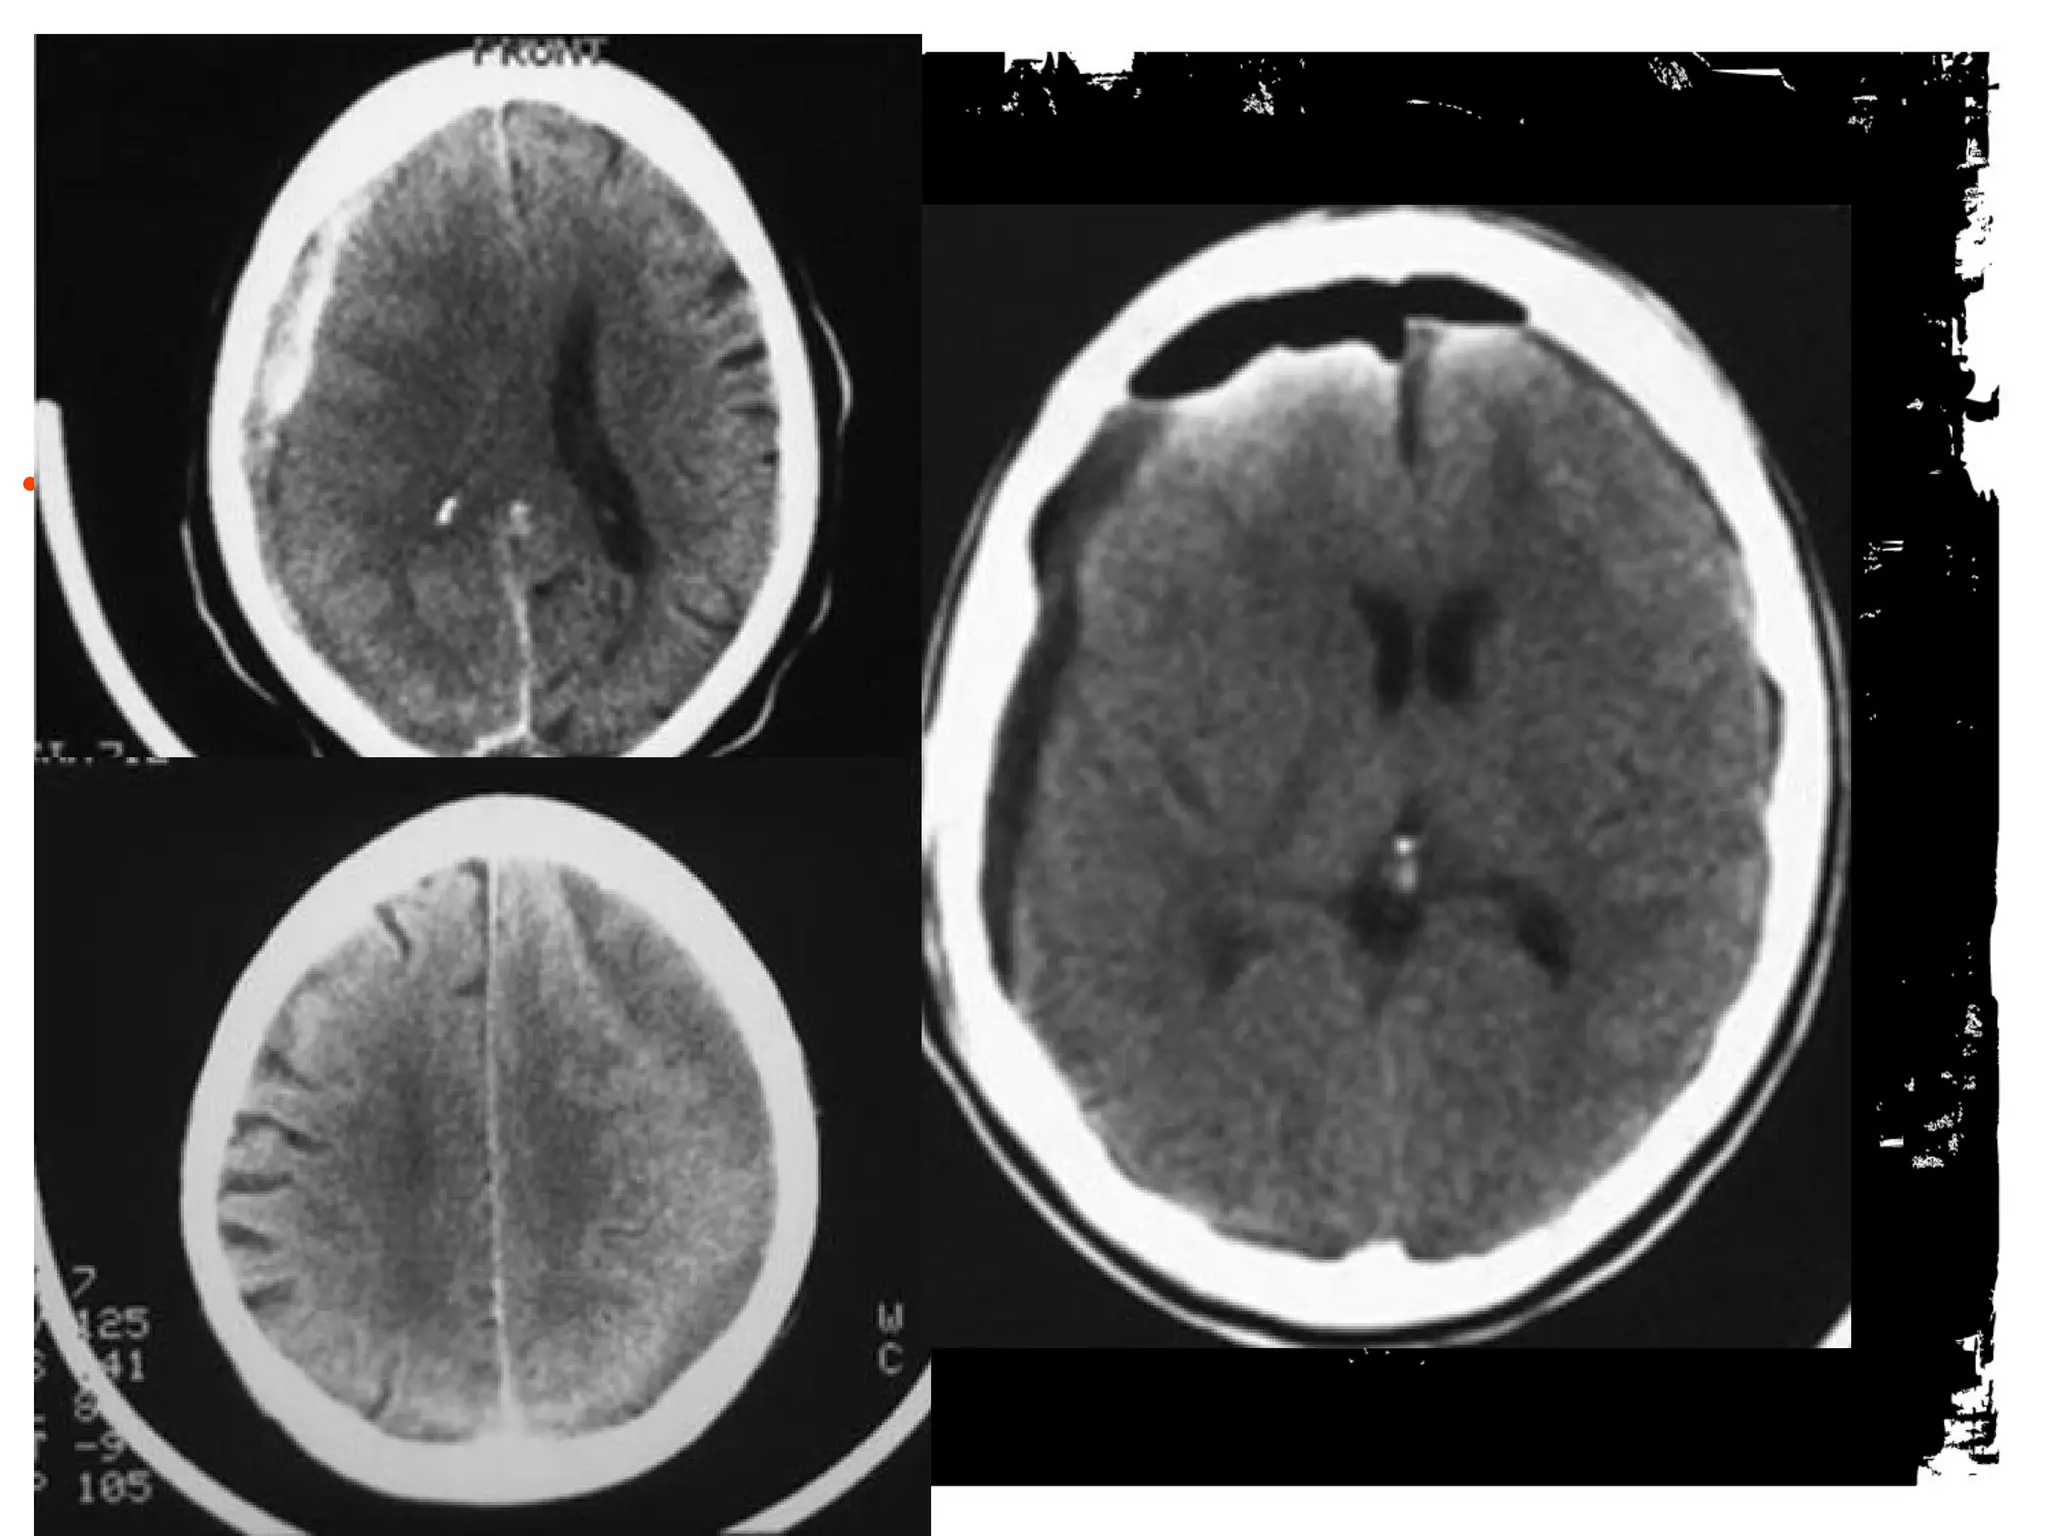

Diffuse axonal injury

Diffuse axonal injury (DAI) is a major form of traumatic

brain injury and is caused by shearing stress primarily in

white matter). Various outcomes are reported (ie, learning

disorders, moderate to severe disability, and vegetative

state) but were unable to correlate the extents of early

injury with the prognoses.

Among patients eventually

proven to have DAI, 50-80%

demonstrate a normal CT scan

upon presentation. Delayed CT

scanning may be helpful in

demonstrating edema or

atrophy, which are later

findings. Small petechial

hemorrhages located at the

gray-white matter junction, as

well as in the corpus callosum

and brainstem, are

characteristic of CT-scan

findings in the acute setting.

Figure 1. Patient 2.

Tong K A et al. Radiology 2003;227:332-339

©2003 by Radiological Society of North America

Figure 2. Patient 4.

Figure 3. Patient 2.